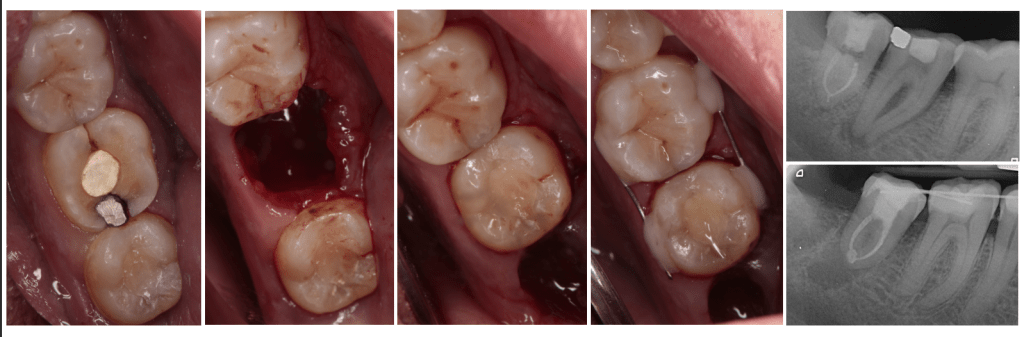

Vertical root fracture